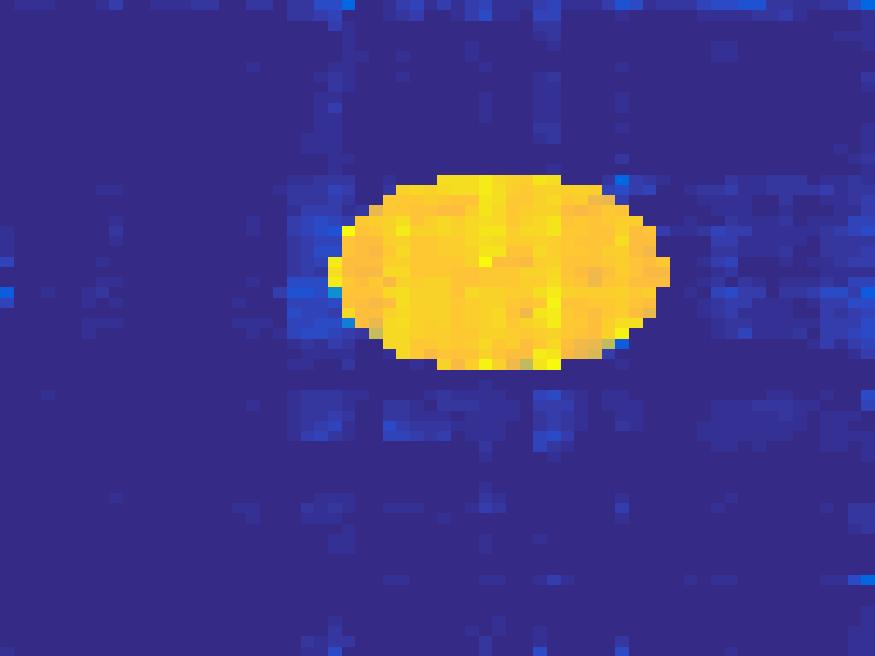

The proposed method is tested on numerical phantoms for a proof of concept study. We simulate image frames of size and projections per frame. Three time activity curves (TAC) for blood, liver and myocardium, previously used in [14] (see Figure 1), are used to simulate the dynamic images. The first simulated dynamic phantom is composed of two ellipses. In temporal direction, the positions of the two ellipses are stationary while the intensity in 90 frames within the region of each ellipse is generated according to the TAC of blood or liver. The projections are generated by using Radon transform sequentially performed for each frame.

In the tests, projections at two orthogonal angles are simulated for every frame to mimic 2-head camera data collection. The projection angles increase sequentially by along temporal direction. For example, at frame 1, projections are simulated at angle and , and at frame 2, angle and , etc. Finally, white Gaussian noise is added to the projection data. Reconstruction results with different methods are shown in Figure 3. Since the number of projections is very limited for each frame, the traditional FBP and least square methods cannot reconstruct the images satisfactorily, while the proposed method is capable to reconstruct the images effectively. Compared with SEMF model, when the edge of images jump (see frame 21 -frame 31 in Figure 3), the proposed model can better capture the change of the tendency of TAC.